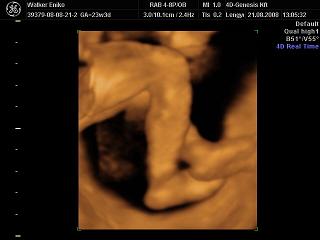

Nagyon helyesek a 4D-s fotók!!!